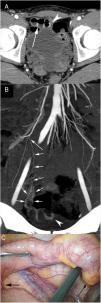

The presence of an MD in a MDCT should be suspected when a blind tubular structure connected to the terminal ileum by a neck of variable size is observed. Multiplanar 2D reconstructions images and CT enterography can help in the diagnosis. In patients with symptoms of obstruction or intestinal inflammation, the possibility of a complication secondary to a MD should be considered, especially when the terminal ileum and the vermiform appendix are normal. MDCT angiography, in cases of acute gastrointestinal bleeding, can identify contrast extravasation and accumulation of blood in the MD, and could demonstrate the persistent omphalomesenteric artery, which is diagnostic of MD. Other MDCT findings such as the presence of enteroliths or associated inflammatory changes around the MD can facilitate the preoperative diagnosis of MD complications.